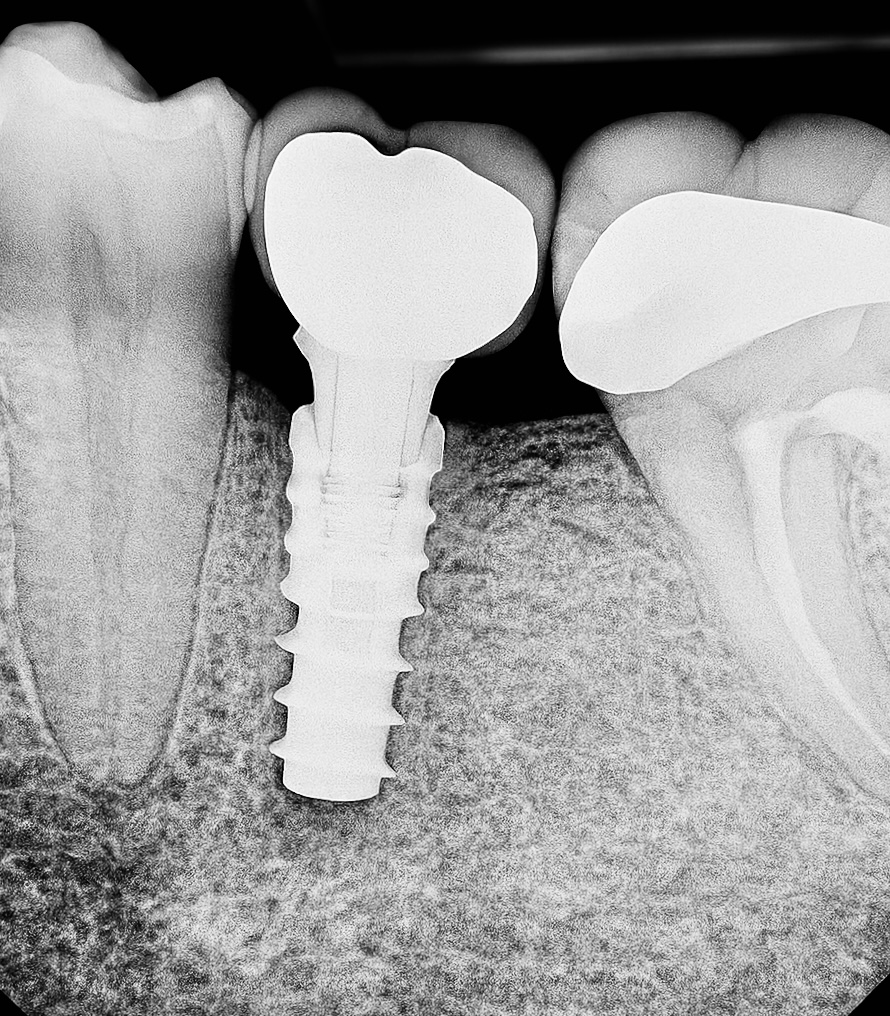

Under local anesthesia, a flapless (minimally invasive) approach was used. Sequential osteotomy performed with copious irrigation following the manufacturer’s torque protocol. A Swiss-made internal-connection implant (4.1 × 11.5 mm) was inserted with 45 Ncm torque for primary stability (Fig 1). Healing abutment placed for transmucosal soft-tissue contouring.

Radiographic follow-up showed precise osseointegration, proper emergence profile, and marginal bone stability (Fig 6). The final prosthesis integrated seamlessly with natural dentition and provided excellent function and esthetics (Fig 7).